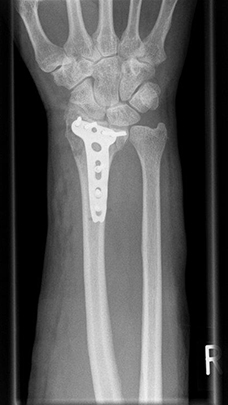

Radiusfraktur nach Korrekturoperation

Radiusfraktur nach Korrekturoperation Frontalansicht

Komplexe rechtsseitige Unterarm-Handgelenksfraktur nach Osteosynthese

Komplexe rechtsseitige Unterarm-Handgelenksfraktur nach Osteosynthese, frontal